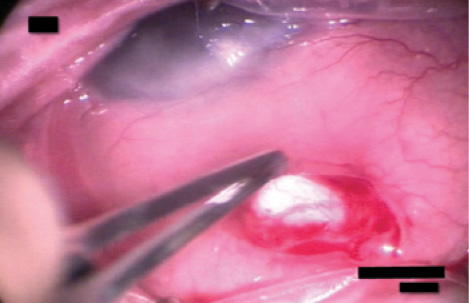

Figure 3. The surgeon uses a limbus-based incision to place a nonvalved glaucoma drainage device.

We therefore elected to perform glaucoma drainage implant surgery using a limbus-based approach to avoid manipulation of the corneal limbal stem cell graft (Figure 3). We placed the tube portion of the device in the ciliary sulcus to decrease the risk of contact with the corneal endothelium.